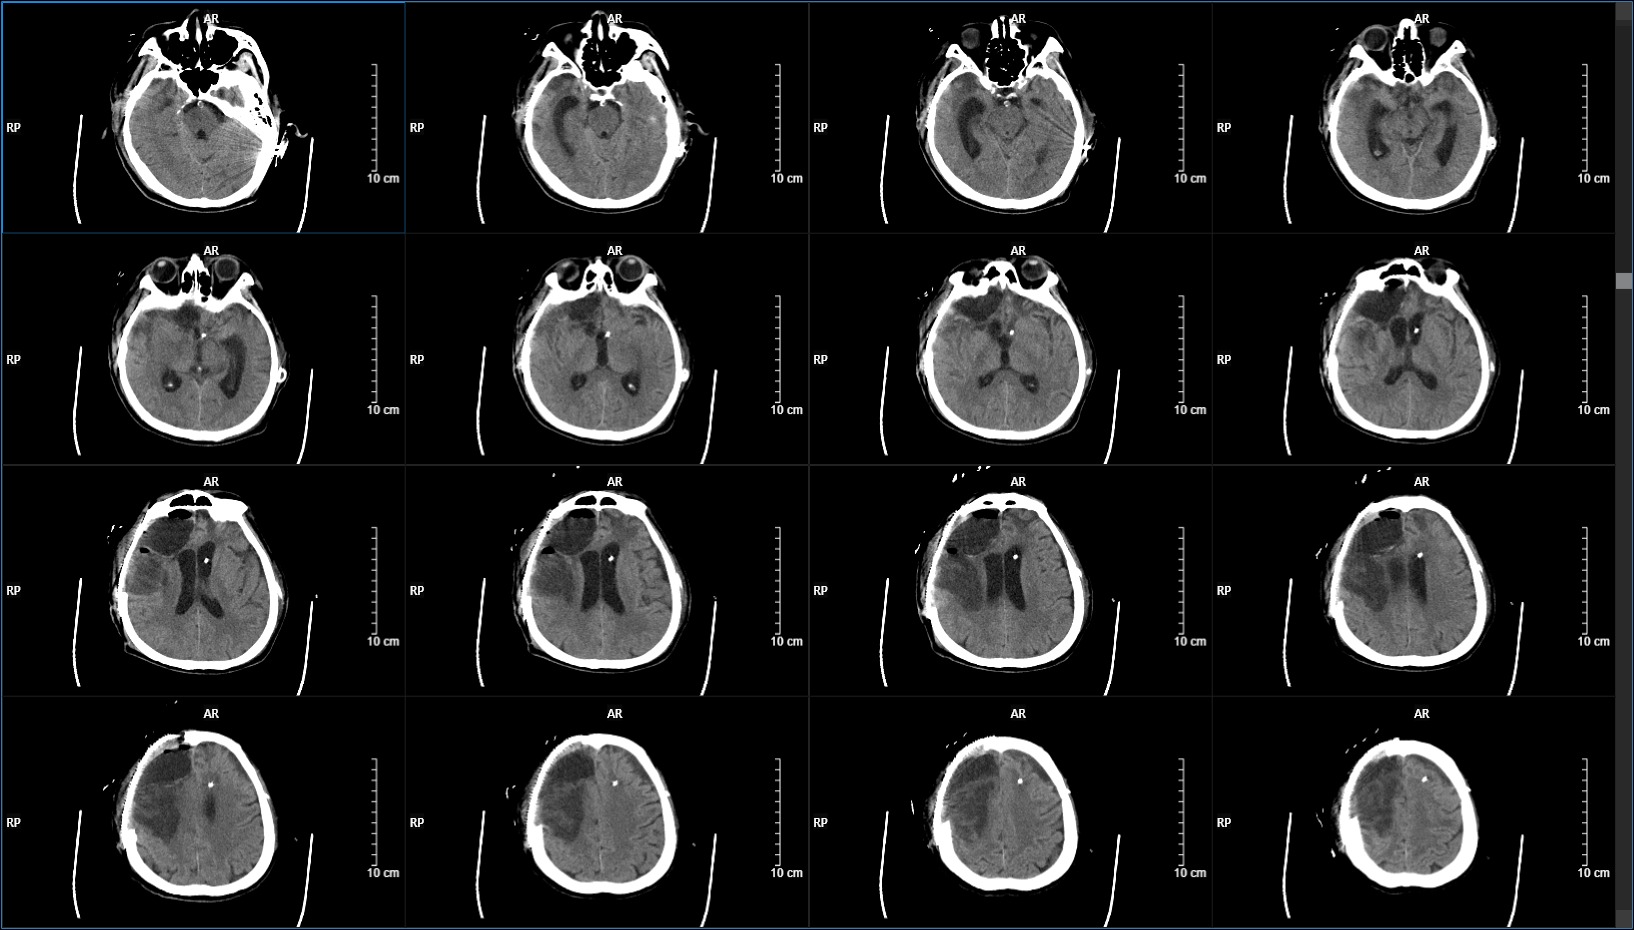

患者因外伤致脑疝、硬膜下血肿、脑挫伤在外院行开颅血肿清除+去骨瓣减压术后2个月,住院期间出现小脑出血(保守治疗),1周后转入我院。入院时 GCS评分8分(E4V1M3),右额颞顶部可见颅骨减压窗压力稍高。双侧瞳孔不等大,左侧直径约2.5mm,右侧直径约3.5mm,对光反射迟钝。

CT显示脑室饱满,颅压220mmH2O,行腰大池引流术,持续引流一周后(期间查脑脊液各项指标均正常),患者症状较入院时好转,查体能简单遵嘱动作,遂行脑室-腹腔分流术。

患者术后症状较前好转,查体能简单发音。